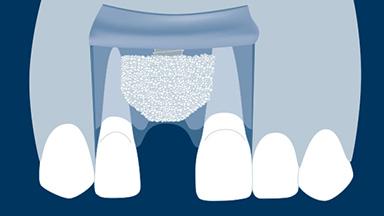

拔牙后,支撑牙齿的牙槽骨会随着时间的推移而发生吸收。这种吸收会导致牙槽骨量减少,如此右上中切牙缺失的临床示例所示。颊舌向骨宽度显著减小,这与将种植体植入以修复为导向确定的正确三维位置的口腔种植基本要求存在冲突。当牙槽骨发生吸收后,通常需要增加骨量以确保可以正确植入种植体且种植体完全嵌入骨中。本模块将介绍一种称为引导骨再生 (GBR) 的特定骨增量技术。

- 描述引导骨再生 (GBR) 的生物学原理